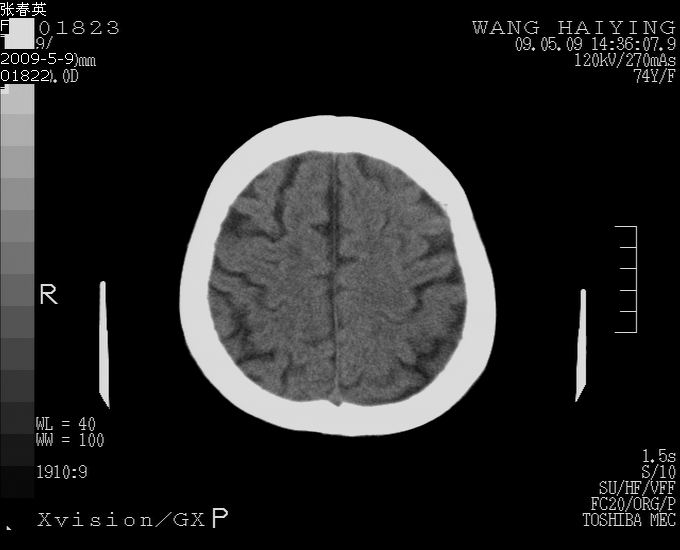

以下是引用bmw011在2009-5-9 18:25:00的发言:[br]脑内多发缺血、梗塞。

以下是引用余辉在2009-5-9 18:32:00的发言:[br]基底动脉稍扩张且右偏,其上方层面见高密度块影,考虑动脉瘤可能,建议增强,皮脑